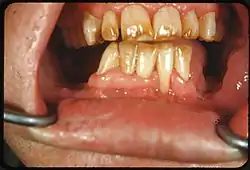

Tooth discoloration is abnormal tooth color, hue or translucency.[1] External discoloration is accumulation of stains on the tooth surface. Internal discoloration is due to absorption of pigment particles into tooth structure.[2][3] Sometimes there are several different co-existent factors responsible for discoloration.[4]

Extrinsic discoloration

Extrinsic discolorations are common and have many different causes.[10] The same range of factors are capable of staining the surface of restorations (e.g., composite fillings, porcelain crowns).[10] Some extrinsic discolorations that are allowed to remain for a long time may become intrinsic.[11]

- Dental plaque: Although usually virtually invisible on the tooth surface, plaque may become stained by chromogenic bacteria such as Actinomyces species.[12]

- Calculus: Neglected plaque eventually calcifies, and leads to formation of a hard deposit on the teeth, especially around the gumline. The color of calculus varies, and may be grey, yellow, black or brown.[12]

- Tobacco: Tar in smoke from tobacco products (and also smokeless tobacco products) tends to form a yellow-brown-black stain around the necks of the teeth above the gumline.[12]